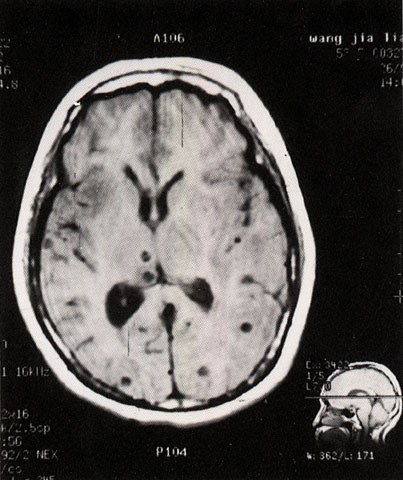

FH1049 脑囊虫病(MRI)

图  名 脑囊虫病(MRI)